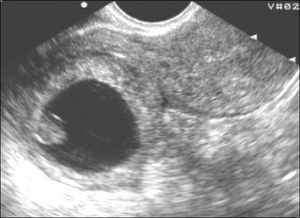

- Ультразвуковое исследование (УЗИ): УЗИ является важным инструментом для визуализации расположения плода. На ранних сроках беременности трансвагинальное УЗИ может помочь выявить наличие эмбриона в матке или за ее пределами. Если УЗИ не показывает эмбрион в матке при высоком уровне ХГЧ, это может указывать на внематочную беременность.

Ранняя диагностика внематочной беременности осуществляется с помощью тщательного ультразвукового исследования, на котором можно увидеть увеличенный яичник и пустую маточную полость.

| Отсутствие плодного яйца в матке при высоком ХГЧ | При УЗИ плодное яйцо не визуализируется в полости матки, хотя уровень ХГЧ достаточно высок. | Трансвагинальное УЗИ. |